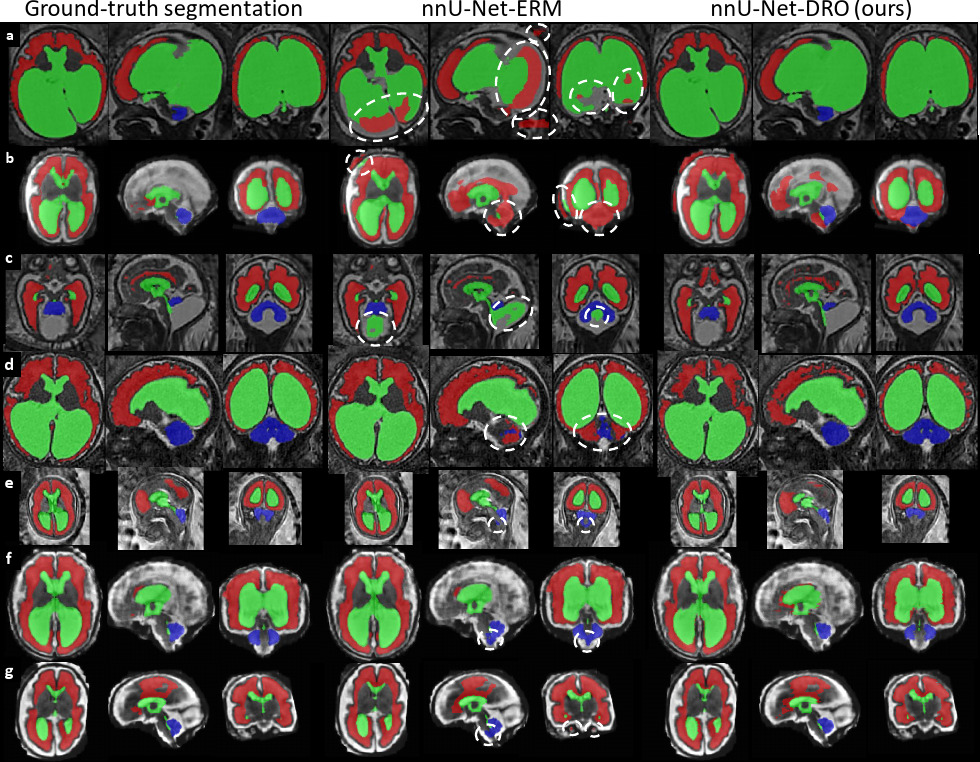

Figure 3: Qualitative Results for Fetal Brain 3D MRI Segmentation using DRO. We have highlighted in white areas with severe violation of the anatomy by nnU-Net-ERM. Most of them are avoided by our nnU-Net-DRO. nnU-Net-ERM and nnU-Net-DRO differ only by the use of the hardness weighted sampler for the latter. a) Fetus with aqueductal stenosis (34 weeks). b) Fetus with spina bifida aperta (27 weeks). c) Fetus with Blake’s pouch cyst (29 weeks). d) Fetus with tuberous sclerosis complex (34 weeks). e) Fetus with spina bifida aperta (22 weeks). f) Fetus with spina bifida aperta (31 weeks). g) Fetus with spina bifida aperta (28 weeks). For cases a) and b), nnU-Net-ERM (Isensee et al., 2021) misses completely the cerebellum and achieves poor segmentation for the white matter and the ventricles. For case c), a large part of the Blake’s pouch cyst is wrongly included in the ventricular system segmentation by nnU-Net-ERM. This is not the case for the proposed nnU-Net-DRO. For case d), nnU-Net-ERM fails to segment the cerebellum correctly and a large part of the cerebellum is segmented as part of the white matter. In contrast, our nnU-Net-DRO correctly segment cerebellum and white matter for this case. For cases e) f) and g), nnU-Net-ERM wrongly included parts of the brainstem in the cerebellum segmentation. nnU-Net-DRO does not make this mistake. We emphasise that the segmentation of the cerebellum for spina bifida aperta is essential for studying and evaluating the effect of surgery in-utero.